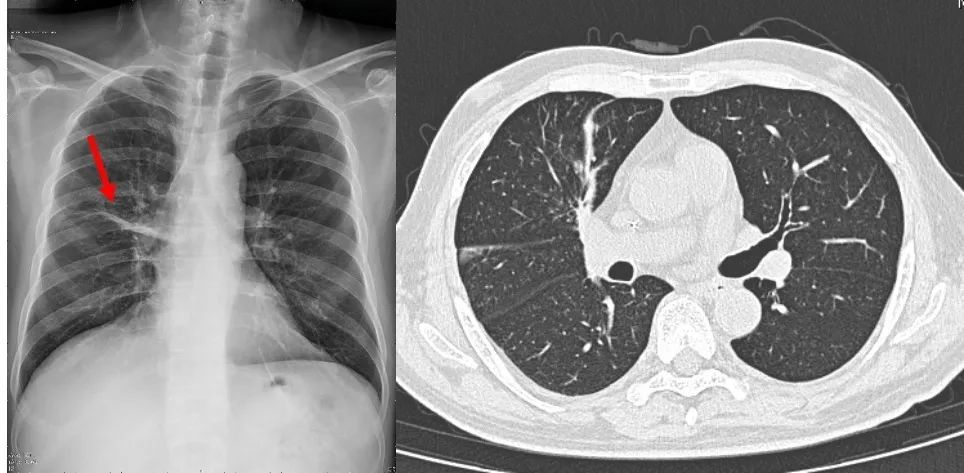

入院时胸片显示右肺病变;治疗1个月后复查胸片及胸部CT显示右肺病变明显吸收